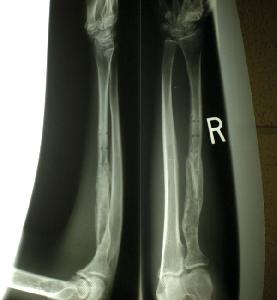

I went to the ortho dr. Last time as my insurance runs out. My arm he said is 95% healed. But now the bone is soft. It takes a full year til it will get the hard white callous like my other bone so a hard fall on one arm, it will break. There is no plate to help it now. I cannot skate ramps yet!!! I am so sad. I shouldnt uni either. Also since I'm malnourished and have no muscle or fat to protect my bones, they will break easy. How do I resolve this? I dont know what makes it heal faster that I can afford now. I'm very poor! Noone else has this problem, I hate it!!!! I want to roll vert again. I'm so sad........ I cried all evening!

Thanx Jay! I think I will see if there is another ortho Dr. in 2 months to look at the xrays. I was skating with the plate in my arm, maybe its a year when he did the surgery that mended my arm. If so that is just 2 more months!